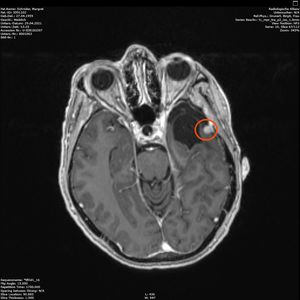

Am 03. November war mein Kontrollbesuch beim MRT. Leider ist ein kleiner Befund aufgetaucht. Schau das Video, dann kannst Du sehen.

Nun kann sich zeigen, ob die menschliche Medizin eine Lösung für mich hat. Möglichkeiten gibt es. Sogar mindestens eine, die der Neurochirurg als fein und elegant beschreibt. Gamma-Knife, eine Strahlentherapie. Klingt etwas nach Star Wars – man wird sehen,  etwas abwarten ist auch drin.

2. November 2021: Leider etwas gewachsen

Heute war ich im MRT im Bremen. Der Befund des auswertenden Arztes ist, dass er der Meinung ist, dass der Tumor etwas gewachsen ist. Ich habe mir die Bilder angesehen und versucht diese Aussage zu verstehen. Vermutlich ist sie richtig, aber das Wachstum ist nicht heftig nur vielleicht von 0,7 cm auf 0,8 cm. Aber Gamma-Knife hat es offensichtlich nicht entfernt.

In der nächsten Woche gehe ich mit denm Bildmaterial zum Neurochirurgen und der wird bei der Auswertung und der daraus folgenden notwendigen Konsequenzen sicher einen Rat haben. Solange muss ich mal abwarten.

Zu meinem Geburtstag am 27.4. habe ich sehr schöne Geschenke bekommen und kann mich auch über meinen bunten Garten freuen, im Herbst gab es ein Tulpen-Sonderangebot, dem konnte ich nicht wiederstehen! Und nun ist das Ergebnis zu sehen. Am 28. April war wieder mal MRT-Termin. Leider hat es an dem Tag eine Vertretung des auswertenden Arztes gegeben, die Ärztin war super freundlich aber hat keine ganz konkreten Aussagen machen können, aber sie hat mir 2 CDs gebrannt, ich konnte eine gleich bei den Neurochirurgischen Ambulanz abgeben und eine mit nach Hause nehmen. Mein Blick auf die Bilder hat eine nazu unveränderte Lage gezeigt.

Heute war der Termin beim Chirurgen, leider schon um 9:00 Uhr und natürlich wollte ich die knapp 20 km mit dem Rad zurück legen, Stephan wollte gerne mitkommen. Leider war die bereits abgegebenen CD nicht eingelesen worden und so musste erstmal die Datenverarbeitung arbeiten und wir warten, bis wir eine Auskunft bekommen konnten. Fazit: Der bestehende Tumor ist kaum gewachsen. Aber es hat sich leider ein 2. Fund ergeben, sehr klein aber deutlich sichtbar. Aber Maßnahmen sind erstmal nicht notwendig.